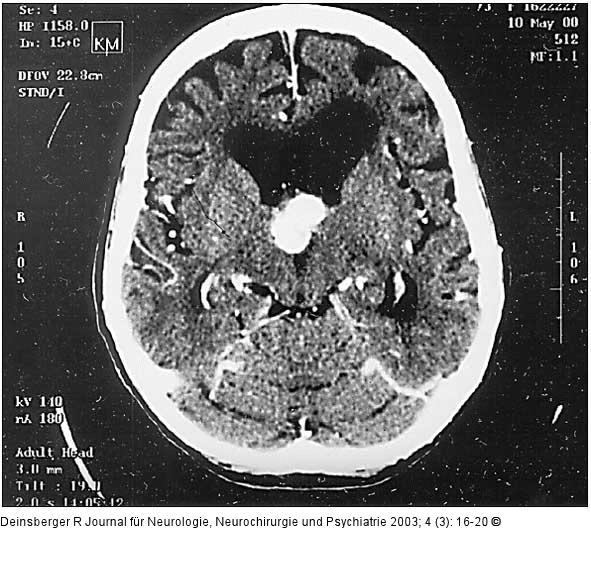

Abbildung 3: Hypernephrom-Metastase

Metastase eines Hypernephroms